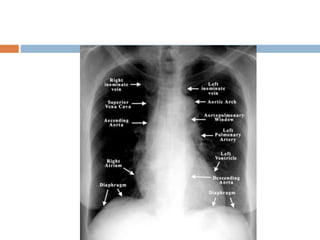

How to read a normal CXR

 This is chest radigraph , PA view with normal

exposure , no rotation and without any

apparent bony abnormality . Trachea is placed

centrally and lung fields are clear with normal

broncho- vescicular markings . Cardivascular

silhoutte is within normal limits with normal

cardiothoracic ratio. Mediastinum, costo

phrenic , cardio phrenic angles , dome of

diaphragm and soft tissue shadow within

normal limits .

How to reada normal CXR  This is chest radigraph , PA view with normal exposure , no rotation and without any apparent bony abnormality . Trachea is placed centrally and lung fields are clear with normal broncho- vescicular markings . Cardivascular silhoutte is within normal limits with normal cardiothoracic ratio. Mediastinum, costo phrenic , cardio phrenic angles , dome of diaphragm and soft tissue shadow within normal limits .